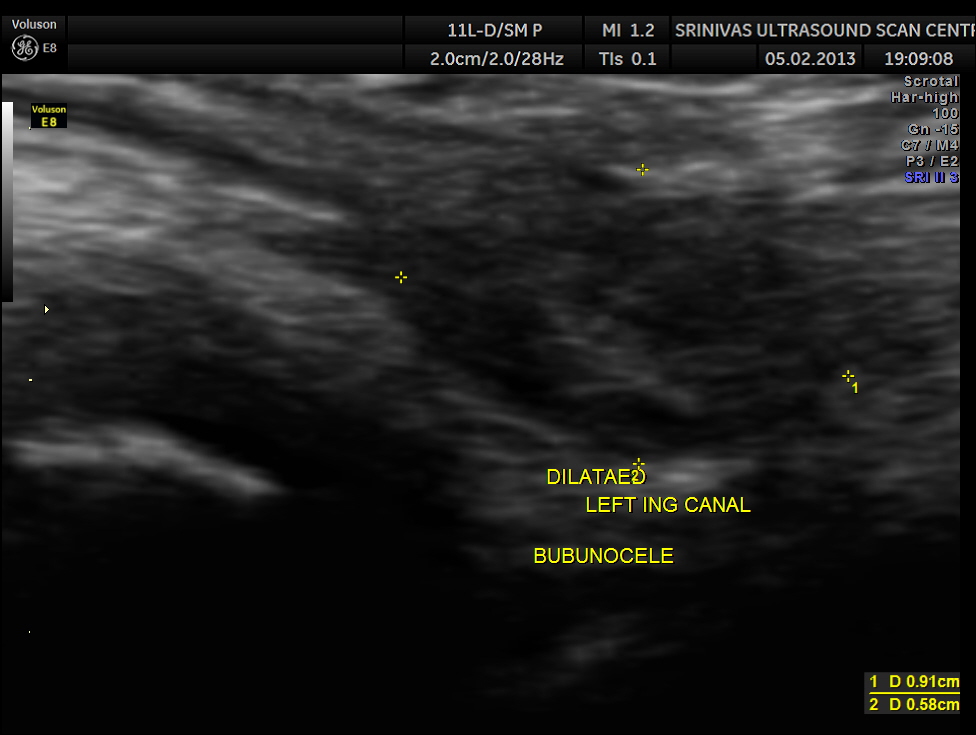

This was a 11 year old boy referred for evaluation of left inguinal swelling on and off.

The clinical diagnosis was bubunocele.

(medicine) An inguinal hernia, especially of the incomplete variety in which the hernial pouch descends only as far as the groin, forming a swelling there like a bubo.

An inguinal hernia, especially one in which the knuckle of intestine has not yet emerged from the external abdominal ring.